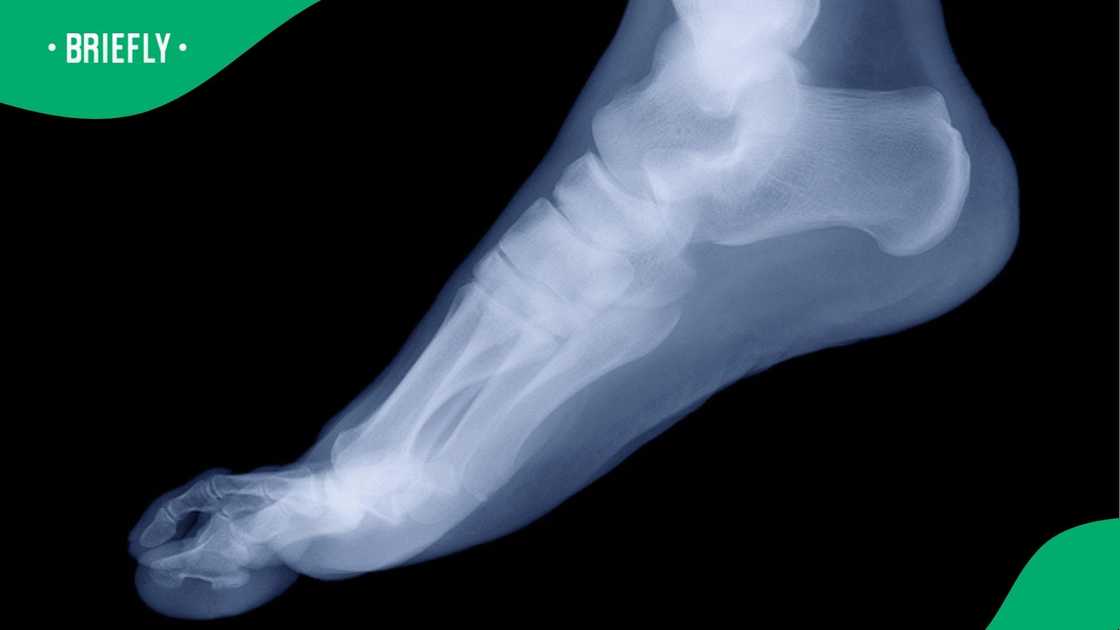

- He explained in a video how much he paid for an X-ray, boot, crutches, and a brief consultation with the doctor

The guy broke down the bill on social media. He explained that his X-ray set him back R1,370, while the boot and crutches cost R3,157.

He was charged a whopping R4,000 for a consultation to see the doctor for just “10 seconds." Totalling it all up, his bill came to R8,527.